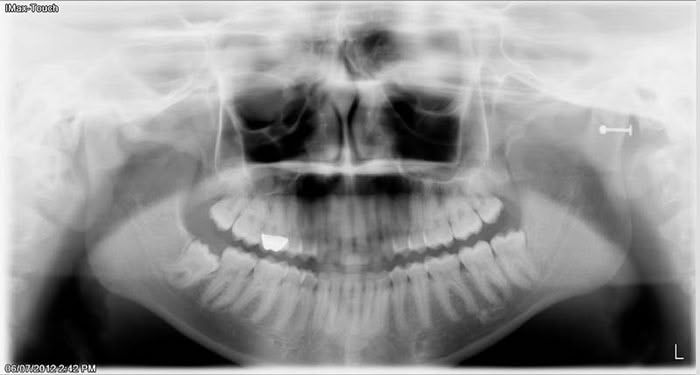

Even before getting to the reasons why wisdom teeth need to be removed sometimes, let’s talk about how dentists and oral surgeons generally diagnose and describe wisdom teeth, aka 3rd molars. The most common x-ray used to see wisdom teeth and figure out if they need to be extracted or not is called a panoramic x-ray. It looks like this: